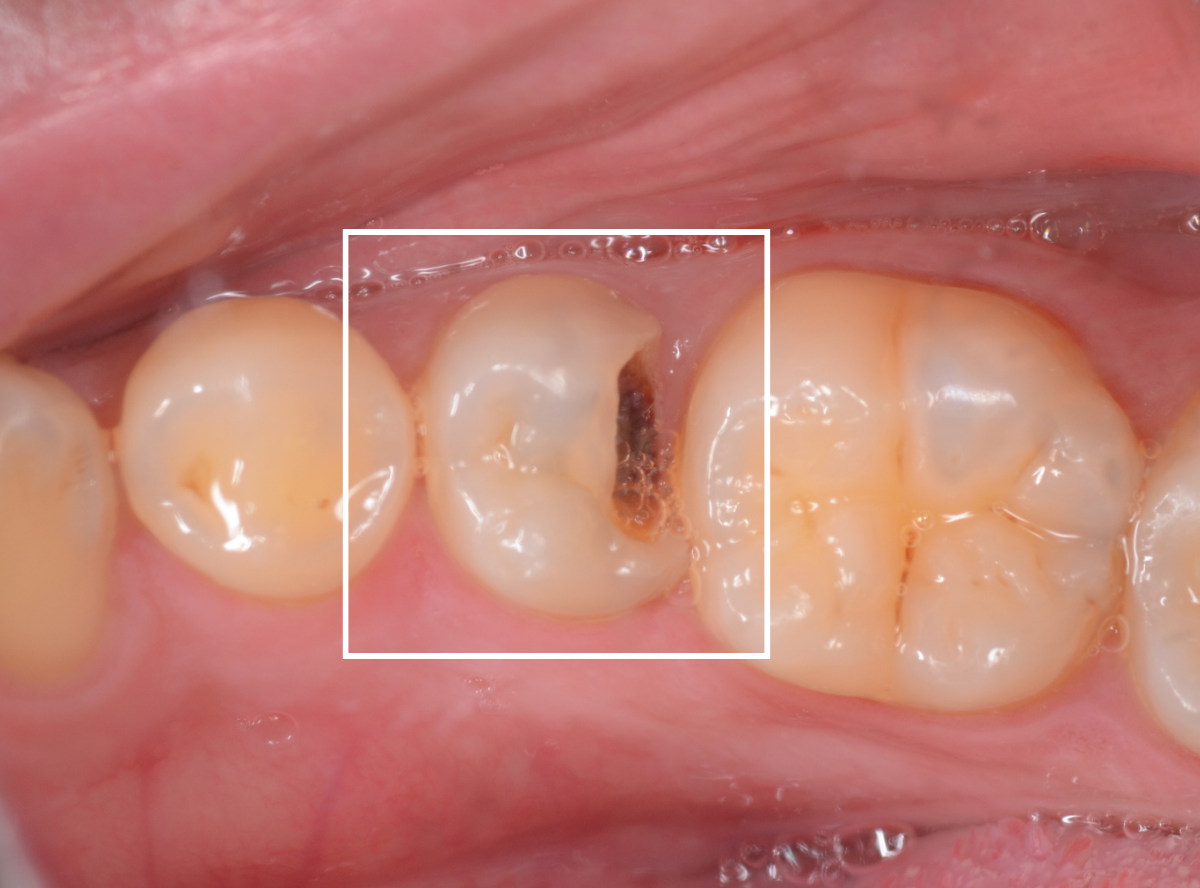

一眼レフカメラと、大画面モニターを使った治療説明

歯の治療って、どこをどんなふうに治療したのか、自分では見えないですよね。

私が患者さんの立場だったら、「どんな風に治療されているのかな」と思いますし、治療を理解する事で、治療脱落防止やメンテナンスを受けるモチベーションにつながりますので、以前から治療の画像を患者さんにお見せして説明する事はしていました。

でも、暗いお口の中の治療の状況を鮮明に撮影してお見せする事は、結構大変で、一般に使われてる歯科用の口腔内撮影用小型カメラは、手軽に撮影できる反面、ぼやっとした荒い画像にしかならず、細かい虫歯の状況などを伝わりづらいのが悩みでした。

色々試行錯誤した結果、多少の手間とデメリットはありますが、一眼レフカメラを使って治療経過撮影をし、治療前後の説明に使っています。

また、以前は一般的ではなかった40インチの大型モニターも、最近は手に入りやすくなりましたので、導入しています。

口腔内カメラで撮った写真を24インチ程度の大きさのモニターで見るのと、一眼レフカメラで撮影した写真を40インチのモニターで見るのでは、患者さんの伝わる情報量が違います。

導入前よりも、患者さんがご自身の虫歯の状況を見て驚きの声を聞く事が多くなりました。

従来の口腔内カメラを使った簡易的な写真 ![]() |

一眼レフカメラを使った口腔内撮影システム ![]() |

一眼レフカメラを使って、可能になった事

写真の解像度が上がったおかげで、大画面でのモニターで細部を拡大して映す事ができるようになり、より詳細に治療の状況をご説明できるようになりました。

患者さんに説明中に、隣の歯の虫歯が見つかる事も。